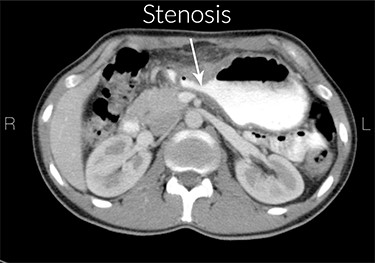

Increased gastric wall thickness was observed with emphasis on antropyloric region and the lesser curvature with maximum thickness of 21 mm accompanied by fat stranding around the same areas. Evidence of partial stenosis with mild dilatation of stomach was seen. Contrast agent has penetrated through the distal region and no leak of contrast agent is observed. Liver, spleen and the pancreas looked normal. No apparent paraaortic lymphadenopathy was observed. No free fluid was observed in the abdomen and the pelvic cavity (Figs 1 and 2).

Stenosis of the gastric outlet. R means right and L means left.